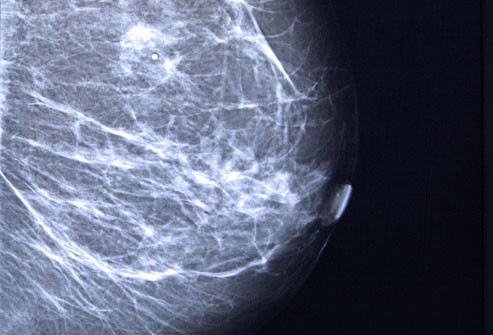

Có rất nhiều loại phẫu thuật ung thư vú, từ đưa ra khỏi khu vực xung quanh các khối u (cắt bỏ khối u hoặc phẫu thuật bảo tồn vú) để loại bỏ toàn bộ vú (mastectomy.) Cách tốt nhất để thảo luận về những ưu và khuyết điểm của từng các thủ tục với bác sĩ của bạn trước khi quyết định những gì phù hợp với bạn.